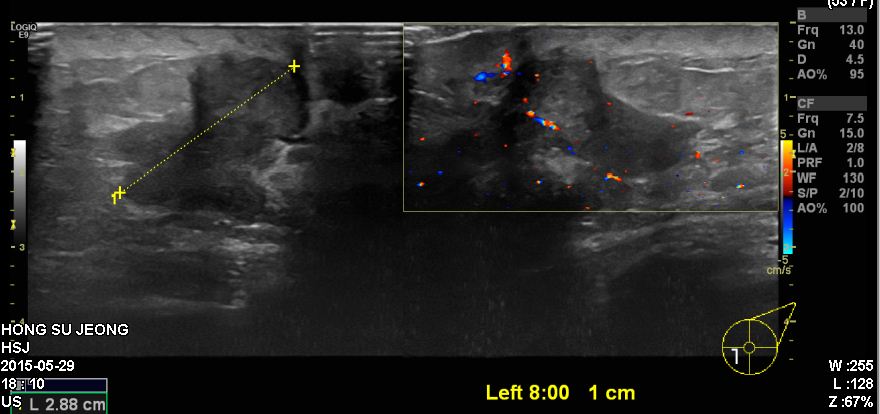

건강검진상 이상 소견으로 내원하신 50대 여성 분으로 좌측 8 :00 방향에 1cm 떨어진

거리에 의심스러운 혹 조직검사 시행하여 좌측 침윤성 유관암 진단 되었습니다.